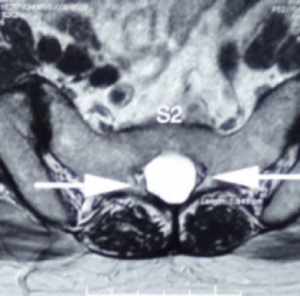

Usually incidental finding in lumbar MRI, one or more Tarlov Cysts will be found in the sacral spinal canal. If they are smaller than 1cm, the patient may not have any symptoms. But if the tarlov cyst grow to more than 1.5cm and it compressed the nerve, this may cause discomfort in patient.

Tarlov cyst generally find at the first to the third section of the sacrum and is filled with cerebrospinal fluid. The swelling can gradually increase and cause the cauda equina nerve to be compressed, causing nerve root inflammation or myelopathy and even affecting the bony structures. Magnetic resonance imaging can clearly distinguish the location, size, and relationship with the dura and nerve roots of the sacral canal.